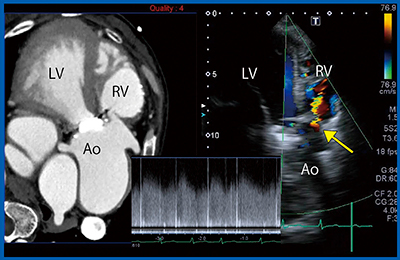

症例3は,62歳,心室中隔欠損症(VSD)術後,大動脈弁置換術後で,労作時呼吸困難と聴診による連続性雑音にて受診した。超音波検査では,paravalvular leakとVSD Residual shuntがあり,さらにValsalva洞に連続性の血流が認められた。Valsalva洞破裂を疑い,直前に撮影したCTとのSmart Fusionを行った(図4)。CTでValsalva洞から右室へ交通を認め,超音波で同部位にshunt flowが明瞭に確認できた。さらに,パルスドプラにより連続性flowが認められたことからValsalva洞破裂と診断できた。

図4 症例3:62歳,VSD術後 大動脈弁置換術後,Smart Fusion